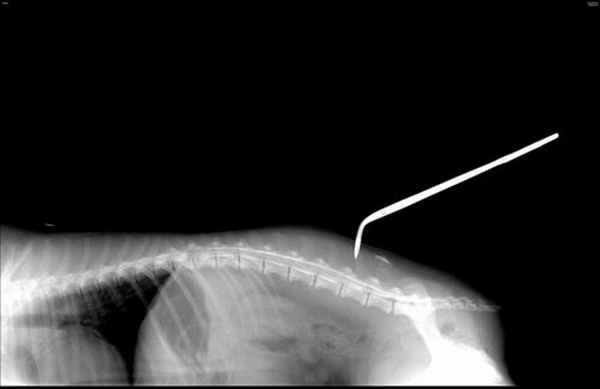

Миелография собак и кошек

Миелография — один из методов контрастного рентгенографического исследования который обеспечивает визуализацию контуров спинного мозга, расположенного в спинномозговом канале позвоночного столба, после введения контрастного вещества между оболочками спинного мозга в субарахноидальное пространство. Показанием к проведению данного метода исследования являются случаи, когда исходя из данных анамнеза и клинического обследования предполагается наличие повреждений спинного мозга, что бы визуализировав, хотя бы его контуры, определить локализацию поражения и выбрать метод хирургического лечения. Данный метод диагностики позволяет точно установить локализацию повреждения, оценить его значимость, а также выбрать технику хирургического вмешательства.

Инъецирование контрастного вещества в субарахноидальное пространство осуществляют двумя доступами: окципитальным (в области шейного отдела позвоночного столба между затылочной костью и первым шейным позвонком) или люмбальным (в области поясничного отдела позвоночного столба). Выбор в каждом конкретном случае индивидуален и зависит от многих факторов.

Рентгенографические снимки сначала выполняют без введения контрастного вещества в 2-х взаимно перпендикулярных проекциях. После введения контрастирующего вещества выполняют серию рентгенологических снимков через определенные промежутки времени в 2-х а иногда и в 3-х проекциях (правая латеральная, вентро-дорсальная, косая проекция) для лучшей визуализации и латерализации поражения.

Просматривая и интерпретируя изображение, полученное в результате проведения контрастного исследования спинного мозга, ветеринарный специалист оценивает прохождение контрастного вещества по субарахноидальному пространству, сравнивает изображение с нормой и отвечает на вопрос в каком отделе позвоночного столба произошла компрессия спинного мозга.